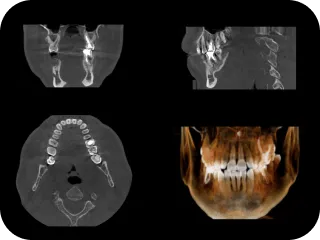

当院では提携のインプラント専門医による手術が可能で、難症例にも対応しております。歯科用CTやマイクロスコープなどの設備を活用し、精密で安心な治療に努めています。